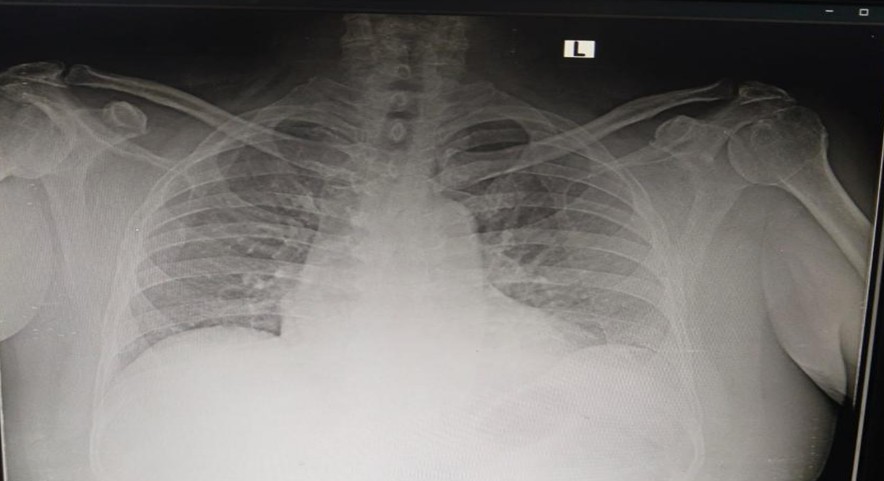

Pre-operative X-ray